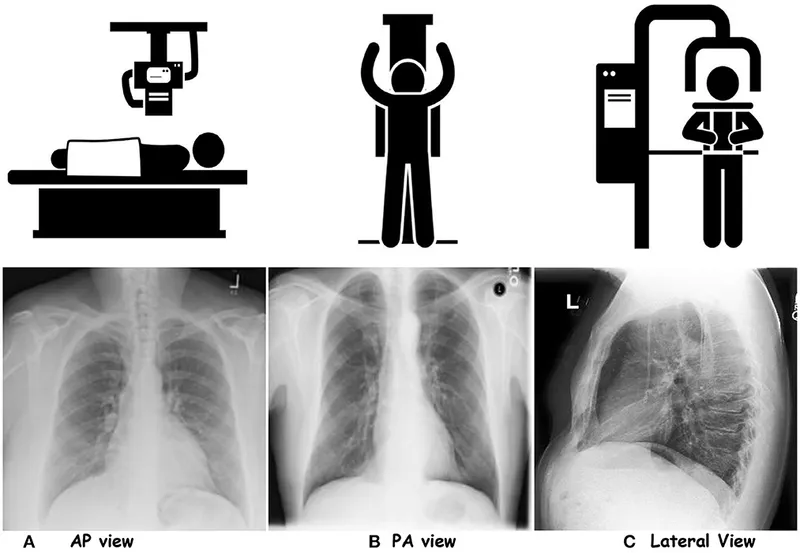

- Standard Views:

- PA (Posteroanterior): Beam passes back to front; preferred view, less cardiac magnification.

- AP (Anteroposterior): Beam passes front to back; often for portable/bedside CXRs.

- Lateral: Left side against detector; complements PA view.

⭐ In AP views, the heart appears magnified because it is further from the detector. This can mimic cardiomegaly.